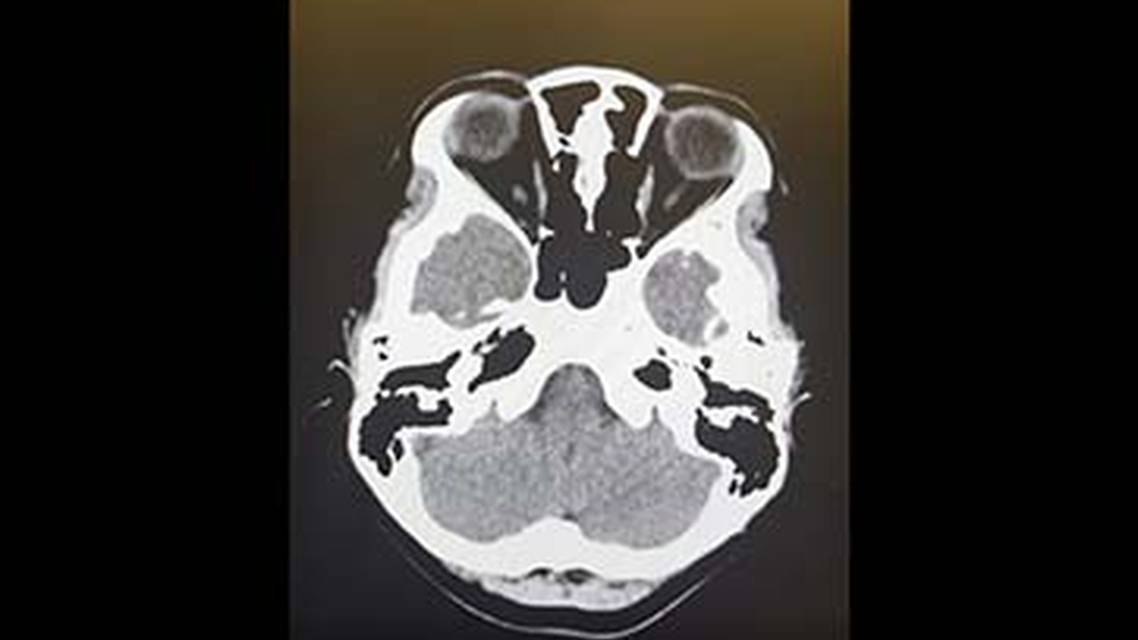

MRI Clues to Intracranial Infection: Differentiating Bacterial, Viral, Fungal, and Parasitic CNS Disease

An Algorithmic Approach to Headache With Fever